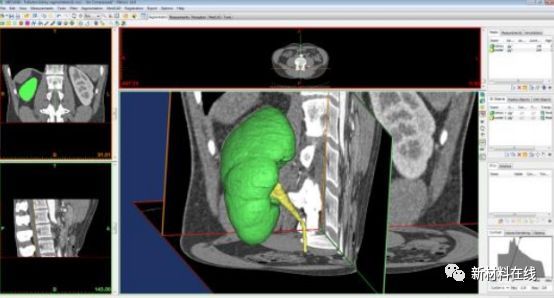

(二)圖像數據信息的處理和轉換

打印物的圖像數據信息還需要根據***終的打印需要進行相應的數據加工處理。醫學領域常用的數據加工軟件有Mimics軟件(Materialise,比利時)、UG Imagewa軟件(EDS,美國)和Geomagic Studio軟件(Geomagic,美國)。

圖片來源: 網絡公開資料